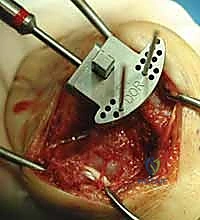

3. الشق الجراحي والوصول للمفصل

يقوم الدكتور هطيف بعمل شق جراحي دقيق في الجزء الخلفي (الظهري) من الرسغ. يتم إبعاد الأوتار والأعصاب بحذر شديد باستخدام أدوات دقيقة لحمايتها من أي ضرر أثناء العملية.

4. إزالة العظام والغضاريف التالفة

باستخدام أدوات جراحية متخصصة، يتم إزالة الصف الأول من عظام الرسغ التالفة، بالإضافة إلى إزالة أطراف عظمة الكعبرة المتآكلة، لتهيئة المساحة لاستقبال المفصل الصناعي الجديد.

5. تجربة المفصل المؤقت

قبل تثبيت المفصل النهائي، يقوم الدكتور هطيف بوضع مفصل تجريبي للتأكد من المقاس الدقيق، واختبار نطاق الحركة، والتأكد من استقرار المفصل وتوازن الأربطة المحيطة به.